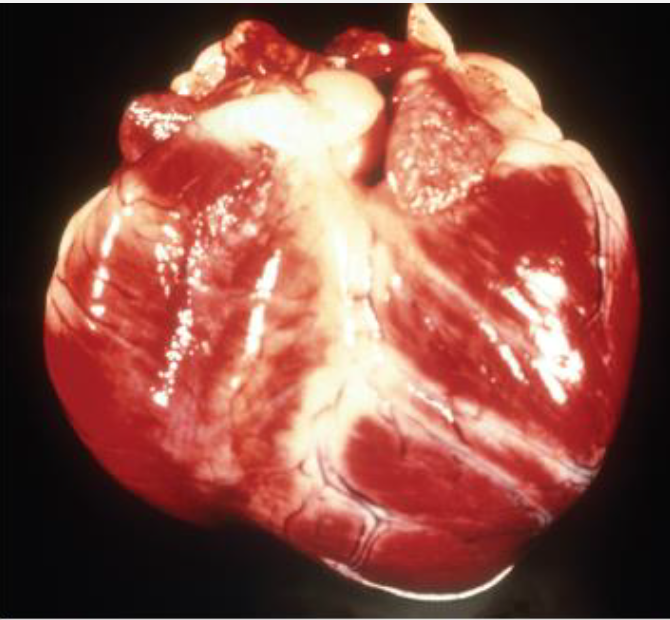

Trypanosoma cruzi infections can cause what clinical signs? Can it infect people?

Causes lymphadenopathy and acute myocarditis

Pale mucous membranes, lethargy, ascites, hepatomegaly, splenomegaly, congestive heart failure

Diagnosis: Trypomastigotes and amastigotes on blood smear or lymph node aspirates, serology, PCR, histopathology

Treatment: No approved treatment, Benznidazole possible (not available in U.S.)

Affected dogs often euthanized